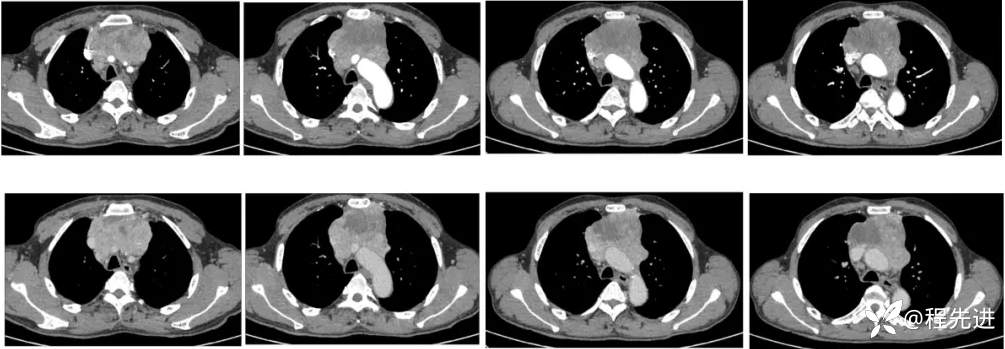

【主诉】:全身乏力近1月,发现纵隔占位20天

【现病史及既往史】:1月前因“脑梗死”就诊于外院进行治疗,住院期间行胸部CT检查提示纵隔占位

影像检查: